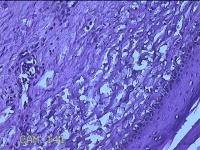

右膝部皮肤肉芽肿

性别

男

年龄

13岁

临床诊断

皮肤肉芽肿

一般病史

外伤后,出现右膝部皮肤肉芽肿形成。

标本名称

大体所见

灰白暗红色带皮肤样组织2.8x1.8x1.3cm,表面糜烂,切面灰白粉红色,质软。

图1